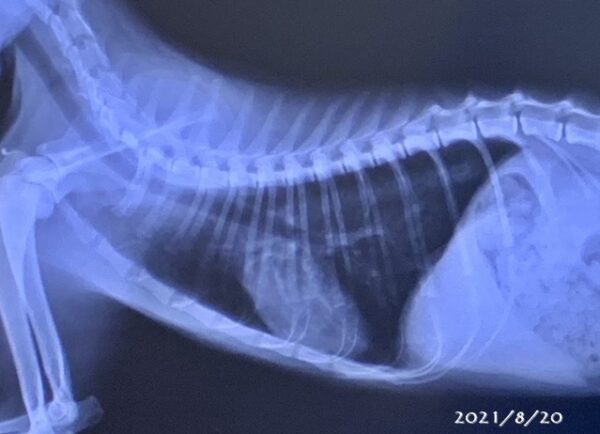

呼吸の悪いうさぎさん 浜村動物病院 うさぎさんのページ